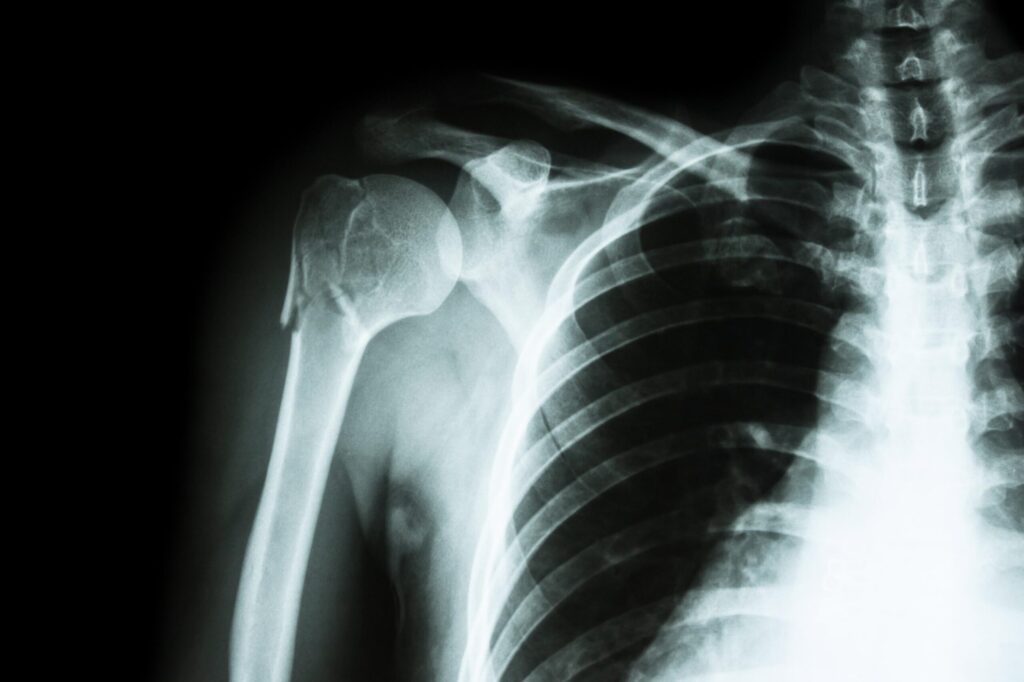

En tant que rédacteur web spécialisé dans le domaine de la santé, il est toujours pertinent d’aborder les multiples facettes du diagnostic médical. L’une des expressions couramment utilisées par les professionnels de santé suite à certaines investigations radiologiques ou échographiques est « absence d’anomalie des parties molles ». Cette phrase, souvent rencontrée dans les comptes-rendus, peut paraître cryptique pour le non-initié, mais elle recèle une signification importante. Le terme « parties molles » fait généralement référence aux tissus qui entourent les os ou les organes – muscles, tendons, graisse et autres structures conjonctives. Ces structures sont essentielles au bon fonctionnement du corps humain et à notre mobilité. Quand un médecin mentionne l’absence d’anomalie de ces parties, cela indique habituellement qu’aucune lésion ni pathologie n’a été détectée dans ces zones, ce qui est une nouvelle rassurante pour le patient. Cependant, comprendre les implications et les limites de cette observation nécessite une exploration plus détaillée des processus diagnostiques en médecine moderne.

Le diagnostic des parties molles est crucial car il permet d’identifier d’éventuelles lésions qui peuvent être la conséquence de traumatismes, d’infections ou de maladies systémiques. L’absence d’anomalie dans ces tissus, qui incluent les muscles, les graisses, les tendons et les ligaments, signifie généralement qu’il n’y a pas de signes évidents de déchirures musculaires, d’hémorragies internes ou d’autres complications. Les techniques d’imagerie comme l’IRM, la tomodensitométrie et l’échographie jouent un rôle primordial dans la fourniture de cette information diagnostique essentielle.

La recherche d’une anomalie des parties molles doit être entreprise quand le patient présente des symptômes tels que la douleur, le gonflement ou une limitation des mouvements. Ces symptômes peuvent indiquer la présence d’une inflammation, d’une infection ou d’une blessure. Il est également important de procéder à des examens réguliers lorsque le patient a une histoire clinique impliquant des maladies qui pourraient affecter les tissus mous, comme le diabète ou des troubles auto-immuns.

Cela signifie que les tissus mous examinés, tels que la peau, les muscles, la graisse et les autres tissus non osseux, n’ont montré aucune anomalie ou pathologie lors de l’imagerie médicale (comme une radiographie, un CT scan, une IRM, etc.). Autrement dit, ces structures apparaissent normales sur les images.